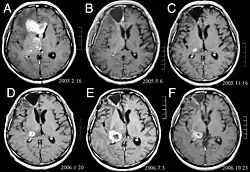

Hirnmetastasen

Hirnmetastasen sind die häufigsten intrakraniellen Neoplasien bei Erwachsenen, die zehnmal häufiger vorkommen als primäre Hirntumoren. Sie treten bei 20 bis 40 Prozent der krebskranken Erwachsenen auf und sind hauptsächlich mit Lungen- und Brustkrebs sowie Melanomen assoziiert. Diese Läsionen sind das Ergebnis der Ausbreitung von Krebszellen durch den Blutkreislauf und treten am häufigsten an der Verbindung der grauen mit der weißen Substanz auf, wo sich der Querschnitt der Blutgefäße ändert und damit Tumorzellembolien eingeschlossen werden. 80 Prozent der Läsionen treten in den Gehirnhälften auf, 15 Prozent im Kleinhirn und 5 Prozent im Hirnstamm. Ungefähr 80 Prozent der Patienten haben eine Anamnese von systemischem Krebs und 70 Prozent haben multiple Hirnmetastasen.

Bei Diagnose und Behandlung dieser Läsionen wurden in jüngster Zeit erhebliche Fortschritte erzielt, wodurch das Überleben und die Kontrolle der Symptomatik verbessert wurden. Das Auftreten von Anzeichen und Symptomen ähnelt denen anderer massiver Läsionen im Gehirn. Das Diagnoseverfahren der Wahl ist die Kernspintomographie unter Verwendung von Kontrastmitteln.

Die Literatur zeigt äquivalente Ergebnisse für Chirurgie und Radiochirurgie. Letzteres scheint bequemer, effektiver und sicherer für kleine Läsionen oder in Regionen zu sein, die für eine Operation nicht zugänglich sind. Die Radiochirurgie ist eine sinnvolle Alternative für Patienten, die aus medizinischen Gründen nicht operiert werden können. Die Operation ist jedoch eindeutig die optimale Methode, um Gewebe für die Diagnose zu erhalten und die Läsionen zu entfernen, die einen Masseneffekt verursachen. Daher sollten Radiochirurgie und Chirurgie besser als zwei komplementäre, aber unterschiedliche Methoden betrachtet werden, die je nach der unterschiedlichen Situation des Patienten angewendet werden.[44] Für fast 50 Prozent der Patienten mit einem oder zwei Hirnmetastasen kommt eine chirurgische Entfernung aufgrund der Unzugänglichkeit der Läsionen, der Ausdehnung der systemischen Erkrankung oder anderer Faktoren nicht in Frage. Diesen und anderen Patienten mit multiplen Metastasen wird normalerweise eine panenzephale Strahlentherapie als Standardbehandlung angeboten. Tatsächlich erreichen bis zu fast 50 Prozent von ihnen mit dieser Therapie eine Verbesserung der neurologischen Symptome und 50 bis 70 Prozent eine erkennbare Reaktion.[45][46][47] Bei Hirnmetastasen wird die Chemotherapie selten primär angewendet.

Bei den meisten Patienten mit Hirnmetastasen beträgt das mediane Überleben nur vier bis sechs Monate nach einer panenzephalen Strahlentherapie. Patienten unter 60 Jahren mit einzelnen Läsionen und einer kontrollierten systemischen Erkrankung können jedoch ein längeres Überleben erzielen, da sie einen aggressiveren Behandlungsansatz vertragen können.